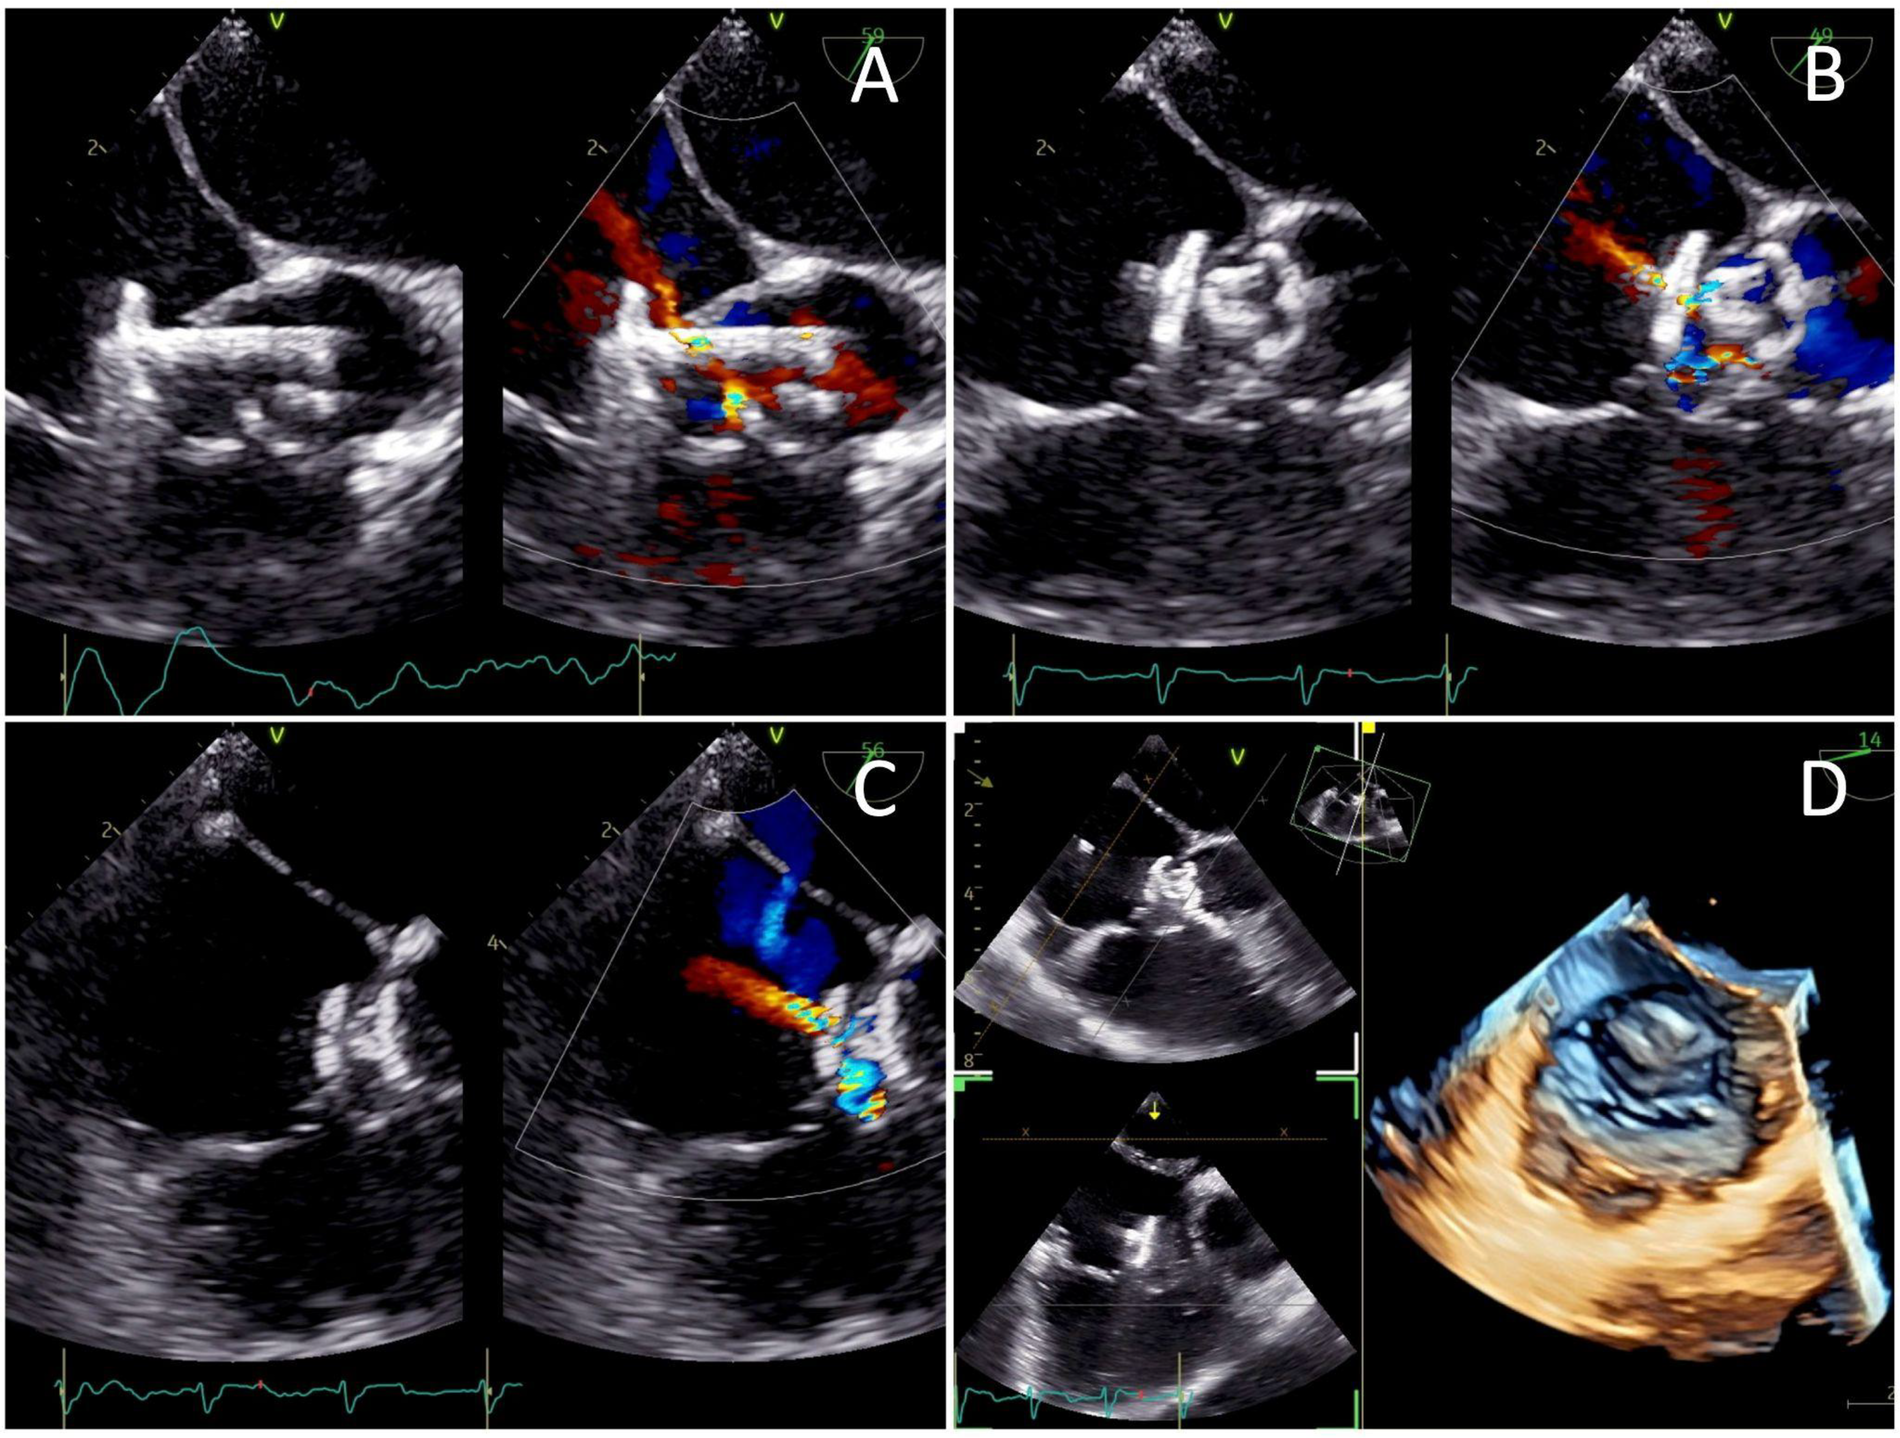

Figure 4

Transesophageal echocardiography views of (A) the low-pressured disc being deployed at the right atrium before the whole system was pulled into the tricuspid valve defect, (B) the high-pressured disc deployed at the left ventricle ends to seal the defect, and (C) a minimal residual central shunt with no peripheral leakage. (D) Post-procedure images demonstrating the device successfully sealing the defect.

2.5 Post-procedure and follow-up

A well-positioned device with minimal residual central shunt and no peripheral leakage was confirmed from the post-procedural TEE (Figure 4). TEE also showed an improved ejection fraction of 70%. The total duration of the procedure was 80 min with an estimated blood loss of 10 mL. The fluoroscopy time was 54 s, and the dose area product (DAP) was 64.41 μGy·m2. The patient's hemodynamics were stable throughout and after the procedure, and he was discharged the following day. At 3 months follow-up, the patient presented without symptoms. TTE evaluation revealed a mild trivial TR, with a maximum velocity (Vmax) of 217 cm/s and a pressure gradient of 19 mmHg. The device was still properly stowed in place, without any residual shunt (Supplementary Video 4). There was no evidence of tricuspid stenosis, thrombus formation, endocarditis, or valve degeneration, indicating an overall good postoperative result.